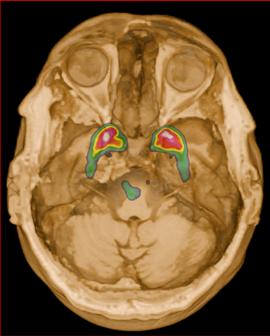

Femenino de 65 años, antecedente de hipertensión arterial de 20 años de evolución en control. Sin antecedentes familiares relevantes de enfermedades neurológicas. Acudió a consulta médica por deterioro progresivo en su capacidad motora y dificultades en las actividades diarias. Desde hace 2 años ha notado cambios en su marcha y en su habilidad para realizar movimientos finos con las manos principalmente del lado izquierdo, rigidez muscular, temblor en reposo siendo mayor del lado izquierdo y dificultad para iniciar y mantener el movimiento, especialmente al levantarse de una silla o al comenzar a caminar. Además, los familiares han observado que tiene una expresión facial inexpresiva y que su voz se ha vuelto más monótona. A la exploración física con expresión facial inexpresiva, temblor de reposo bilateral en manos de predominio izquierdo, rigidez muscular generalizada, más pronunciada en las extremidades superiores, bradicinesia evidente en la realización de movimientos finos de las manos, marcha festinante con pasos cortos y arrastrando los pies, reflejos osteotendinosos normales, no se observan déficits sensoriales. Se realiza adicionalmente la escala de Evaluación de la Enfermedad de Parkinson (UPDRS) con un total de 35 puntos, indicando moderada afectación de la enfermedad. Inicialmente se realiza una tomografía simple de cráneo, sin alteraciones estructurales, al no encontrar algún hallazgo se decide realizar posteriormente Resonancia Magnética Cerebral 1.5 Tesla: sin alteraciones estructurales significativas. Por este motivo y ante la alta sospecha clínica se realiza estudio de imagen molecular PET-RM con 6-[18F] FDOPA en equipo 3 Tesla en el cual se observa la disminución de la captación de la 6-[18F]FDOPA a nivel de putamen y caudado de predominio derecho evidenciando la degeneración dopaminérgica nigro presináptica a este nivel, con un patrón tipo 2 (Egg shaped) así como la mala definición de nigrosoma, estos hallazgos compatibles con enfermedad de parkinson. (Figura 1 y 2)

Actualmente, el diagnóstico del Parkinson se basa principalmente en métodos convencionales que incluyen: -Presencia de 2 de los 3 síntomas principales, con ausencia

axial fusionada de PET-RM 3T con

con disminución de la captación del radiotrazador a nivel de ambos putámenes en la región posterior y media de predominio derecho así como disminución en el caudado ipsilateral.

2. Reconstrucción tridimensional avanzada de imagen híbrida PET-RM 3T con 6-[18F]FDOPA observando disminución de la captación del radiotrazador a nivel de ambos putámenes en la región posterior y media así como en el núcleo caudado derecho.

Figura 1. Imagen

6-[18F]FDOPA

Figura

Figura 3. Reconstrucción mediante imagen molecular de imagen híbrida PET-RM 3T con 6-[18F] FDOPA observando disminución de la captación del radiotrazador a nivel de ambos putámenes en la región posterior, media y anterior así como en ambos núcleos ca dados de predominio derecho.

Figura 4. Reconstrucción mediante imagen molecular de imagen híbrida PET-RM 3T con 6-[18F]FDOPA observando captación adecuada y conservada del radiotrazador en el cuerpo estriado (ambos putámenes y núcleos caudados) en un paciente negativo para enfermedad de parkinson.